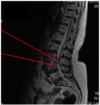

fracture of C2 axis

hangmans fracture

hangmans fracture

- Fracture through the pars interarticularis

- Unstable fracture

- Forward displace of C1 and C2 on C3

clear X-ray of hangmans fracture

cause of hangmans fracture (C2)

usually caused by forcible hyperextension of the neck, classically caused through hanging, giving it its unusual lay name.

Why does is a hangmans fracture very unlikely to damage the spinal cord

because the fracture itself expands the spinal canal, so it typically presents with neck pain alone.

diagnosis of hangmans fracture

Diagnosis is confirmed with an X-ray or sometimes a CT scan.

treatment of hangmans fracture

Treatment can range from a neck brace to neck immobilisation (a form of skeletal traction) to surgical intervention